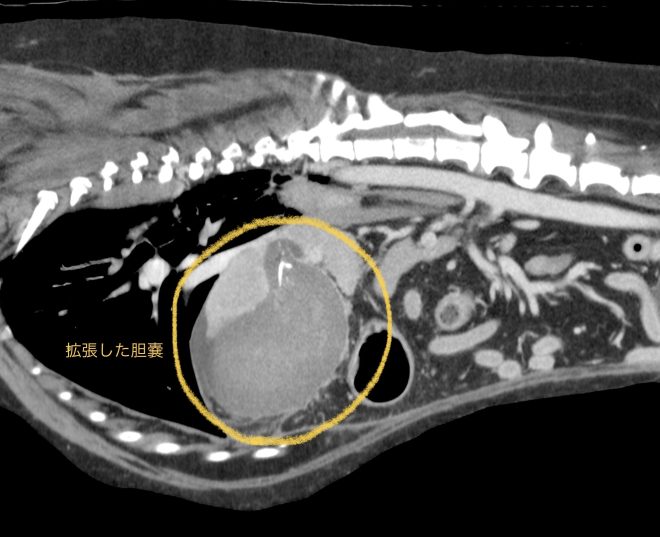

今回治療させて頂いたワンちゃんは、胆嚢粘液嚢腫の経過観察中に胆嚢破裂が生じ、緊急手術を行いました。胆嚢は粘液貯留により重度に拡張し、胆嚢壁の血流が悪くなり壊死が生じた結果、破裂していました。手術で胆嚢摘出を行ったあと、数日は胆汁性腹膜炎が続きましたが、術後6日で無事に退院されています。